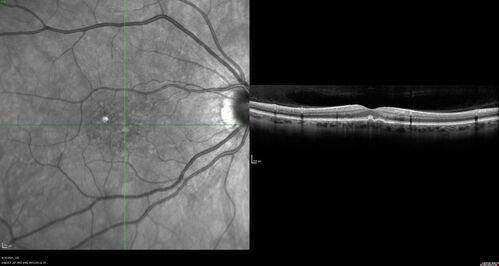

60 year old healthy man with intermediate AMD and peripheral pigment degeneration and pavinstone degeneration.  Vision is 20/20 OU and the patient is asymptomatic.  No significant history of AMD and he is a non-smoker.

Peripheral reticular pigment degeneration - pavingstone degeneration - age-related macular degeneration